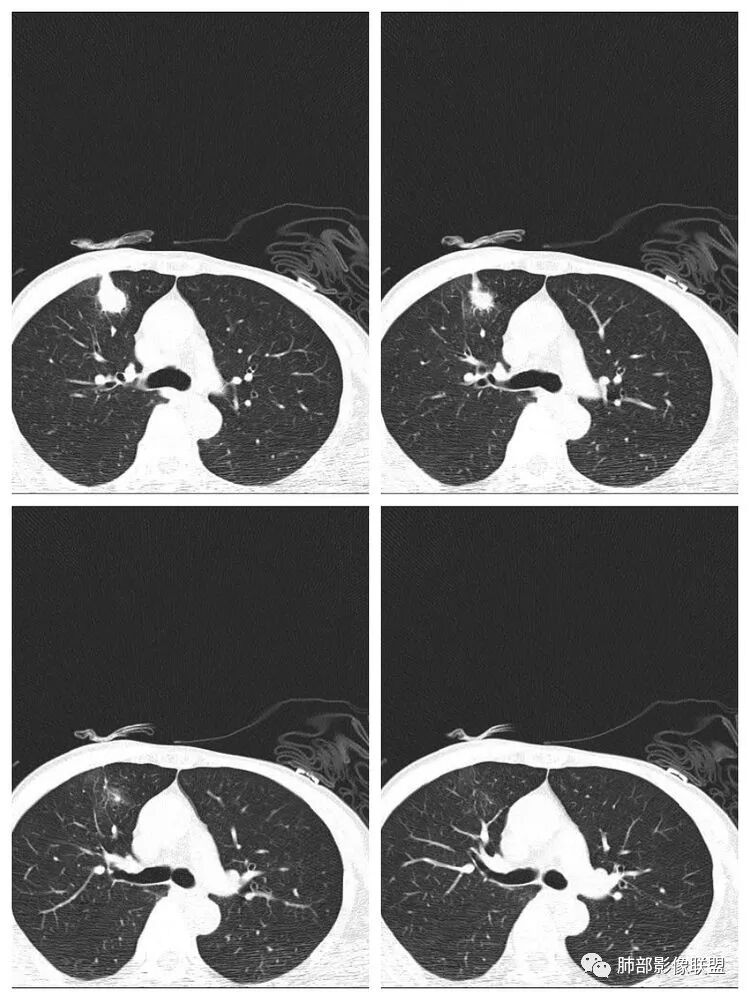

老年男性,有胃癌可惜没增强南边:常规:1、转移瘤2、肺癌3、炎性病变为啥考虑炎性?小赵:局部边缘平直南边:

南边:有密度差,外围密度高

南边:

南边:宽基底与胸膜相连桃尖征、U型凹陷、刀切征密度均匀,按理这一部分就是典型的炎性病变的特点

这一部分如何分析?

南边:周围晕、细微毛刺都属于炎性特点这一部分单独拿出来类圆形,边缘光滑,按理恶性特征不明显;但是加在一起,转移瘤就不排除总体倾向于炎性,转移瘤不除外

南边:就目前的征象符合炎性,我认为炎性病变一定有但是有部分边缘膨隆,恶性不能排除,等炎性吸收后看看,或穿刺血管纠集南边:

南边:我们担心的,它是在一个转移的基础上,还有合并有炎症,担心这个隐藏在其中,因为它这个边缘,是不是很清楚光滑哈,但是我们都记得转移瘤,他很多都是边界清楚光滑的,对不对。就觉得,中间这个结节跟周围的病灶好像形态、密度各方面都不一致的。我就担心它是一个转移瘤,合并感染,周围炎性病变,中间是一个转移瘤结节这样的就麻烦了。所以常规我会建议他抗炎治疗后复查。看看那个残留的病灶怎么样,本质是如何,要么穿刺,这个病变我只能说炎性它一定有。南边:里面那个病灶就是那个类圆形的病灶,跟外面那个肯定是不一致的,就那个类圆形病灶,到底是一个转移瘤,还是单纯炎性病变的部分。目前这个片只能等复查,毕竟边缘是膨隆的,而且我们刚才也说了,转移瘤的特点,如果血道转移,他就是边界清晰光滑的。所以成这样,有这么巧的话你就没办法。南边:关于血管纠集,它就这样的,炎性病变也可以这样表现,牵拉过来,原理不同,但是影像表现已经表现很类似,我们往往关注支气管。支气管进入这个病灶的表面的时候是否堵塞,或者血管,进入这个病灶里面,是否走行是否自然;这些这些可能价值大一些,但是他是不是一个恶性征象,是;但是它的比例就是在炎性病变也不低。原发呢,不敢说没有,但是一般来说几率偏低吧。